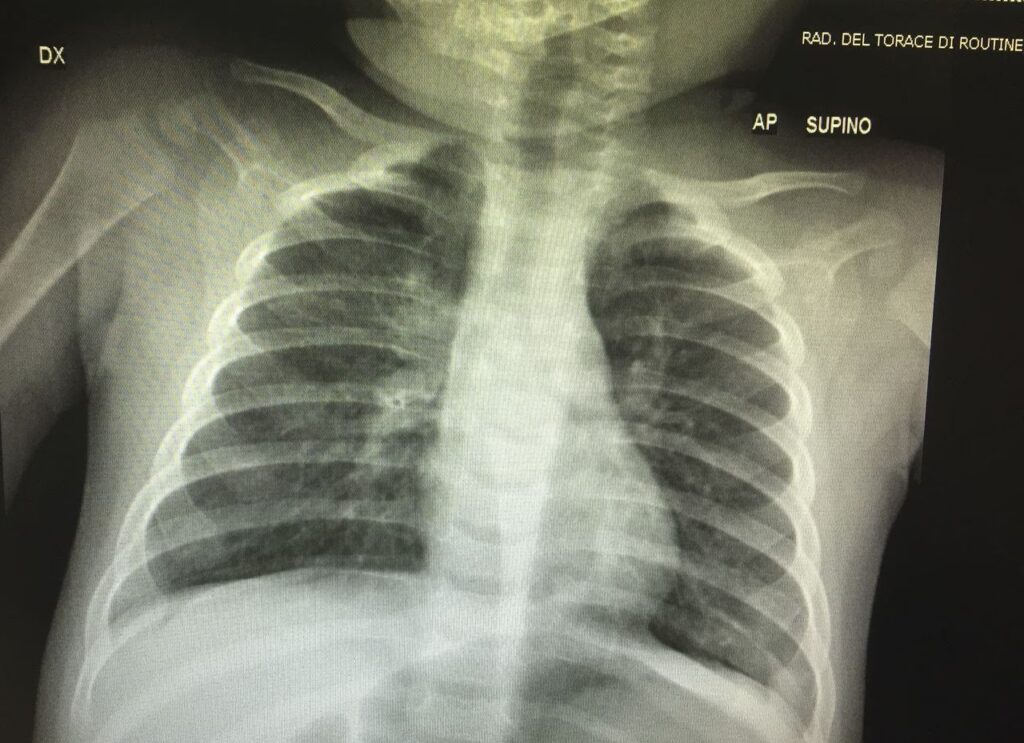

Røntgen af Brystkassen: Et Værktøj til Komplikationer

Et centralt spørgsmål for mange er, hvad et røntgenbillede af lungerne kan vise. Det er vigtigt at understrege, at et røntgenbillede typisk tilføjer meget lidt til selve diagnosen af ukompliceret kighoste. Et billede kan se helt normalt ud, selv hos en person med alvorlige hosteanfald. Derfor bestilles et røntgenbillede kun, når der er klinisk indikation, f.eks. hvis patienten har behov for ilttilskud, har feber, eller lægen mistænker en komplikation som lungebetændelse.

Når et røntgenbillede tages, kan det afsløre flere ting:

- Perihilære infiltrater eller ødem: Dette er det mest almindelige fund. Det betyder, at der er tegn på inflammation eller væskeansamling i området omkring hilum – det centrale område i lungen, hvor de store luftveje og blodkar træder ind. Dette kan give et 'busket' eller 'uigennemsigtigt' udseende på billedet.

- Atelektase: De kraftige hosteanfald og slimdannelse kan blokere små luftveje, hvilket får dele af lungen til at klappe sammen. Dette kaldes atelektase og ses som et tættere, hvidt område på røntgenbilledet.

- Konsolidering: Hvis der ses en mere solid, afgrænset fortætning i lungevævet, er det tegn på konsolidering. Dette indikerer typisk en sekundær bakteriel lungebetændelse, som er en almindelig og alvorlig komplikation til kighoste. I sjældne tilfælde kan det være selve kighoste-bakterien, der forårsager en decideret lungebetændelse (pertussis pneumoni).

- Sjældne komplikationer: I meget sjældne tilfælde kan den ekstreme trykændring under hosteanfald føre til, at en lunge punkterer (pneumothorax) eller at der slipper luft ud i brysthulen omkring hjertet (pneumomediastinum).

Sammenligning af Røntgenfund ved Kighoste

| Røntgenfund | Hvad det betyder | Betydning ved Kighoste |

|---|---|---|

| Perihilære infiltrater | Inflammation/væske omkring centrale luftveje | Almindeligt fund, men ikke specifikt for kighoste. |

| Atelektase | Dele af lungen er klappet sammen | Forårsaget af slimpropper og kraftig hoste. |

| Konsolidering | Solid fortætning i lungevævet | Tegn på en sekundær lungebetændelse (komplikation). |

| Pneumothorax | Punkteret lunge | Sjælden, men alvorlig komplikation pga. tryk fra hoste. |

Det er afgørende at huske: et normalt røntgenbillede udelukker ikke kighoste. Diagnosen hviler på det kliniske billede og en positiv PCR-test.